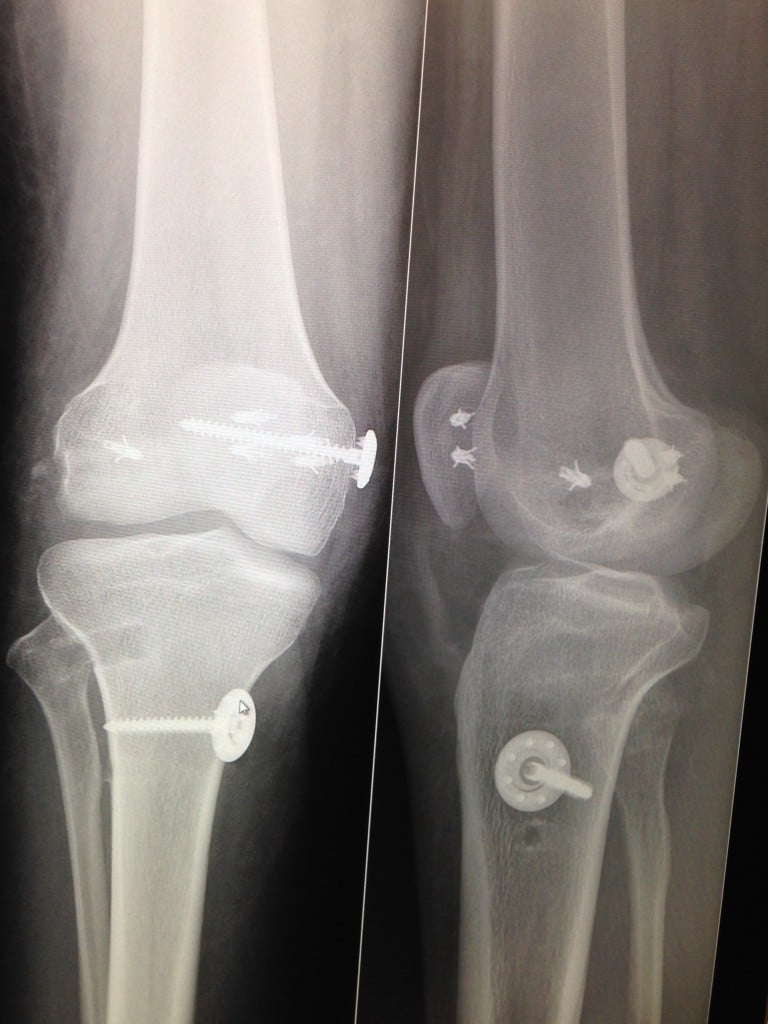

I was born with a knee problem that no doctor could figure out. My right knee was always a different shape, couldn't bend all the way, and never gained nearly as much muscle as my left leg. I have been in pain every single day of my life and not knowing if my pain could ever stop was very frustrating. I tried sports but my knee didn't cooperate and I've tried dance. I was able to run and do things like everyone else except not as long. When I was younger they told me the pain was just from "growing pains". I've had doctors tell me my knee was worn out like a 40 year old and another doctor tell me I will have to live with the pain forever. Well as I got older it became worse and worse with the amount of knee pain and I knew taking medication like Tylenol and ibuprofen could only last so long because it wasn't solving the problem. I'm from Long Island and I saw a few doctors at HSS and they referred me to other doctors there. When I was 17 I had found the doctor I was looking for and from the first visit I knew he was going to help me. He spent almost thirty minutes talking to me about my knee and the issues he already saw. I've been through so many X-rays and cat scans in my life that it has been so many I lost count! So he ordered that I get some pictures taken to see what was going on. Well he told me my bone structure was a little off, I had LAX ligaments, and my knee cap he could do a complete reconstructive surgery. I had never gotten surgery before but for the second time with Dr. Rodeo, I had trust and felt comfortable. My first surgery was over seven hours on March 28, 2014. Recovery was painful and being so small I got side effects to all the medication, it was insane, I would never even wish the pain I went through on anyone in the world. I knew going through all that physical and mental pain it would pay off. When I came back home on the Island my physical therapist would bet other people that I wouldn't go back, people would think I have a good pain tolerance but no. I had a procedure done to manipulate it to bend more summer of 2013. This summer in 2015 I got my screws taken out and it has been less painful, I go to the gym a few times a week to strengthen it up. I still can't bend it all the way and I have long scars on my knee but it was worth it. My senior year of High School when my first surgery was done I used to pull over from driving, could hardly walk upstairs to my room, and it was hard to focus in school. I was also told I wouldn't be able to walk my graduation and wear heels to prom and did both! I thank Dr. Rodeo and all the staff at HSS because now I am back to being me and back in the game.